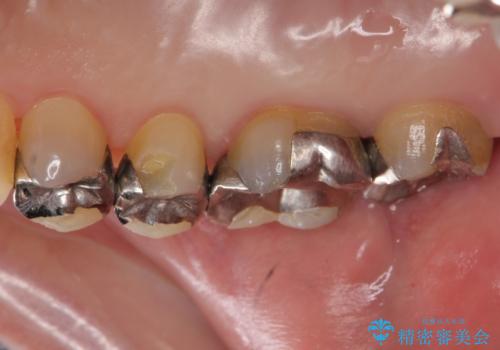

銀の詰め物を外し、欠けたところを覆うように新しい詰め物を作成します。

- 右上5 ゴールドアンレー 77,000円費用は治療当時の料金となります

欠けたところに金属を使用することで、再度欠けてしまうリスクを抑えました。